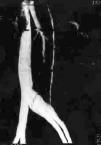

Figura 1. TAC abdómino-pélvico de la paciente; se observa trombosis de vena ovárica derecha y su relación con anejos y útero.

Tras comprobar la normalidad en las constantes maternas y el registro cardiotocográfico fetal, se instauró perfusión endovenosa con oxitocina según protocolo. A las siete horas postingreso se indicó la finalización del parto mediante cesárea con el diagnóstico de parto estacionado, obteniéndose un feto hembra de 3.315 g, Apgar 9-10, pH-venoso 7,36 y pH-arterial 7,29. La intervención y el puerperio inmediato transcurrieron sin incidencias. Se mantiene tratamiento con analgesia, hierro y enoxaparin 20 mg/24 h vía subcutánea. A las 72 horas postcesárea inicia síndrome febril con patrón en agujas sin otra sintomatología clínica, no encontrándose a la exploración ningún foco séptico. Se cursan hemocultivos, radiografía de tórax, sedimento urinario, cultivos de loquios y del seroma de herida quirúrgica que resultan ser negativos. Asimismo se inicia cobertura antibiótica con ceftriaxona y clindamicina. Ante la persistencia del cuadro febril como única manifestación clínica se practica TAC abdómino-pélvico que informa de la existencia de una trombosis de la vena ovárica derecha, que abarca todo su trayecto, con evidencia de trombosis parcial de la vena cava inferior a nivel de su confluencia con la vena ovárica. Se inicia tratamiento anticoagulante con heparina sódica: 20.000 UI/24 h EV en bomba de perfusión continua a 21 ml/h en suero glucosado al 5 por 100 (500 ml/24 h). Para descartar microembolismos se practica gammagrafía pulmonar ventilación-perfusión y ecocardiograma, que resultaron normales.